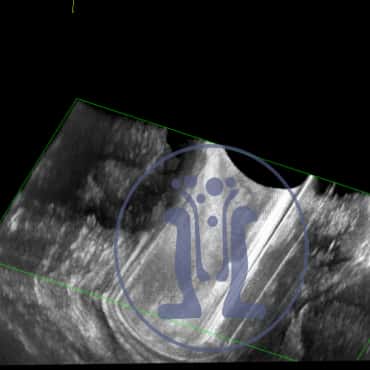

Ασθενής, πάνω από 70 ετών παραπέμπεται από άλλο συνάδελφο για χαρτογράφηση. Στο ιστορικό τυ αναφέρει απόστημα στο δεξιό γλουτό προ 20ετίας και πρόσφατα φλεγμονή και παροχέτευση αποστήμαατος στον αριστερό γλουτό. Στην δική μας εξέταση ανευρέθηκε επιπλέον δερματικό στόμιο στην 6η ώρα που ειχε ξεφύγει από την προσοχή. Στην διερεύνηση ανευρέθηκε βαθύ συρίγγιο με πρωκτικό στόμιο στην 6η ώρα.